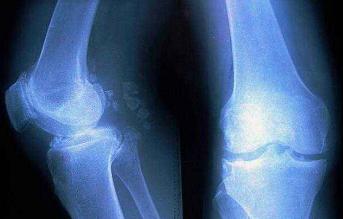

3、骨关节炎继续发展,整个关节的关节软骨都会磨损或消失,X线片上可以看到膝关节内、外侧的关节间隙均变窄,有强烈的疼痛感,保守治疗不能缓解,不适合做单髁置换术或截骨术,则应该选择将膝关节全部关节表面进行替换,即全膝关节置换术。